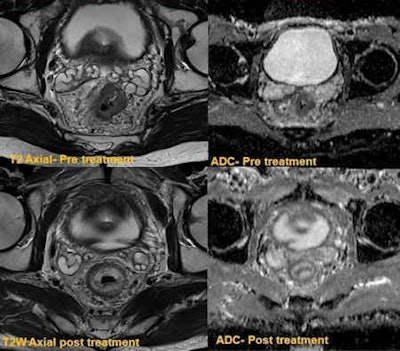

The top row shows low rectal tumor with restricted diffusion. The bottom row shows follow-up T2-weighted image demonstrating minor residual mucosal thickening. DWI shows no residual restricted diffusion, indicating post-treatment scarring."Peri-tumor fibrosis, desmoplastic reaction, edema, inflammation occur following combined chemoradiotherapy. This poses a considerable diagnostic challenge in restaging because these post-treatment responses can produce spiculated margins and the signal characteristics resemble residual tumor on T2-weighted images. Hence overstaging is potential problem," wrote Jacob, whose co-author was Dr. Muthukumarasamy Balasubramaniam, a specialist registrar at the same institution. "DWI overcomes this pitfall as these changes do not demonstrate restricted diffusion, and the ADC values are generally high, proving to be a useful clinical tool."

The top row shows circumferential tumor with significant restricted diffusion. The bottom row was obtained following downstaging chemoradiotherapy, which confirmed complete response. There is no residual tumor on postresection histology."There have been major recent advances in focal and endoscopic techniques, with procedures such as transanal resection of tumor (TART) and transanal endoscopic micro surgery (TEMS) now becoming an increasingly common first line of treatment. However there are substantial challenges in surveillance of these patients," they noted. "Post-treatment fibrosis can often be difficult to differentiate for residual tumor on endoscopy or standard MRI. DWI can be of considerable value in follow-up of this group of patients."